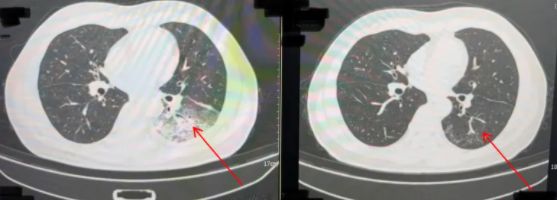

胸部CT显示李先生的左肺已出现大面积白色影像,几乎占据一半肺部。经过肺泡灌洗NGS检测,最终确认“罪魁祸首”是嗜肺军团菌。

李先生肺部治疗前与治疗后的对比

周先生治疗前后的肺部CT影像。图源:央视网